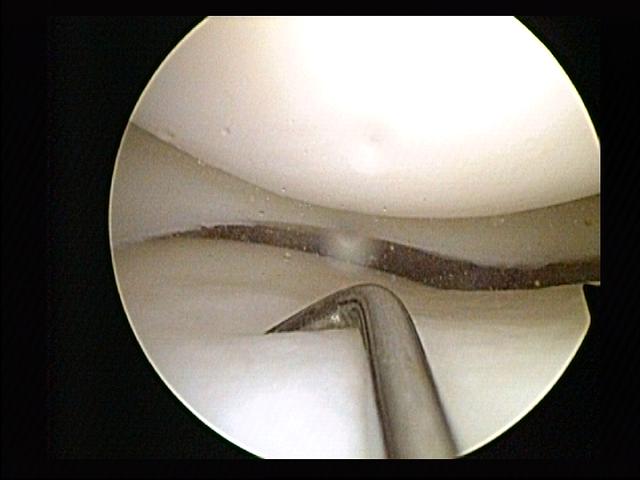

Cirugía Artroscópica

Realizamos este tipo de cirugías, cuya principal característica es que son mínimamente invasivas en las que se logra reparar alguna articulación como la rodilla, hombro, etc.

Al ser poco invasivas tienen ciertas ventajas como: una recuperación más rápida, riesgo bajo de infección y el sangrado es mínimo.